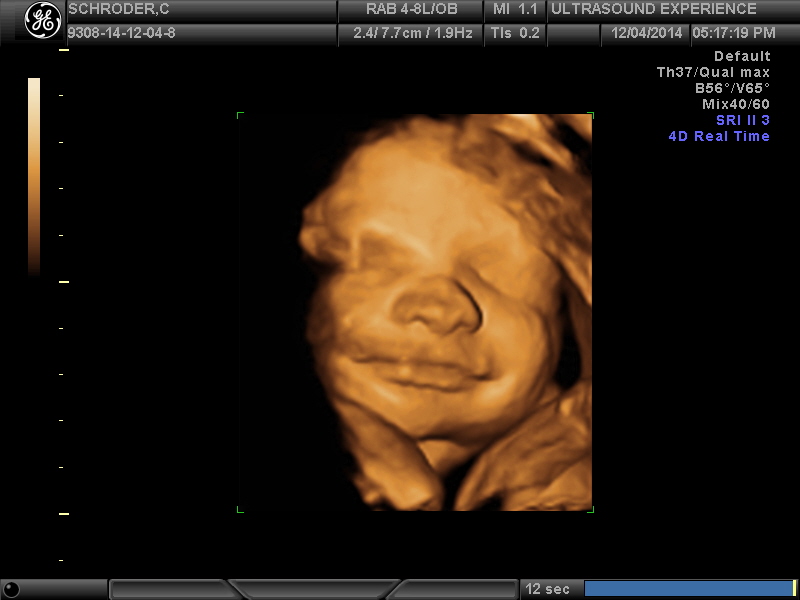

we saw you today

…and it was amazing. As if we couldn’t love you anymore…we do. Seeing your precious face in 4D was an incredible experience. We saw your facial features and they are so defined! You already have expressions that resemble mine and your dads and it was so awesome to see that 🙂 You are unbelievably adorable with a full head of hair, pronounced nose and mouth and scrumptious cheeks. You were very active during the ultrasound and were wiggling around and moving your tiny hands and feet non-stop. You smiled for us and even threw up a peace sign…just like your mama 🙂

It makes waiting another 9 weeks (give or take) even harder because we just want to meet you now!

All the grandparents joined us at the 4D & they are so in love with you also. We went out after to celebrate at an amazing sushi & robata japanese restaurant and you may have tasted the way too spicy shishito pepper I ate, sorry baby 😦